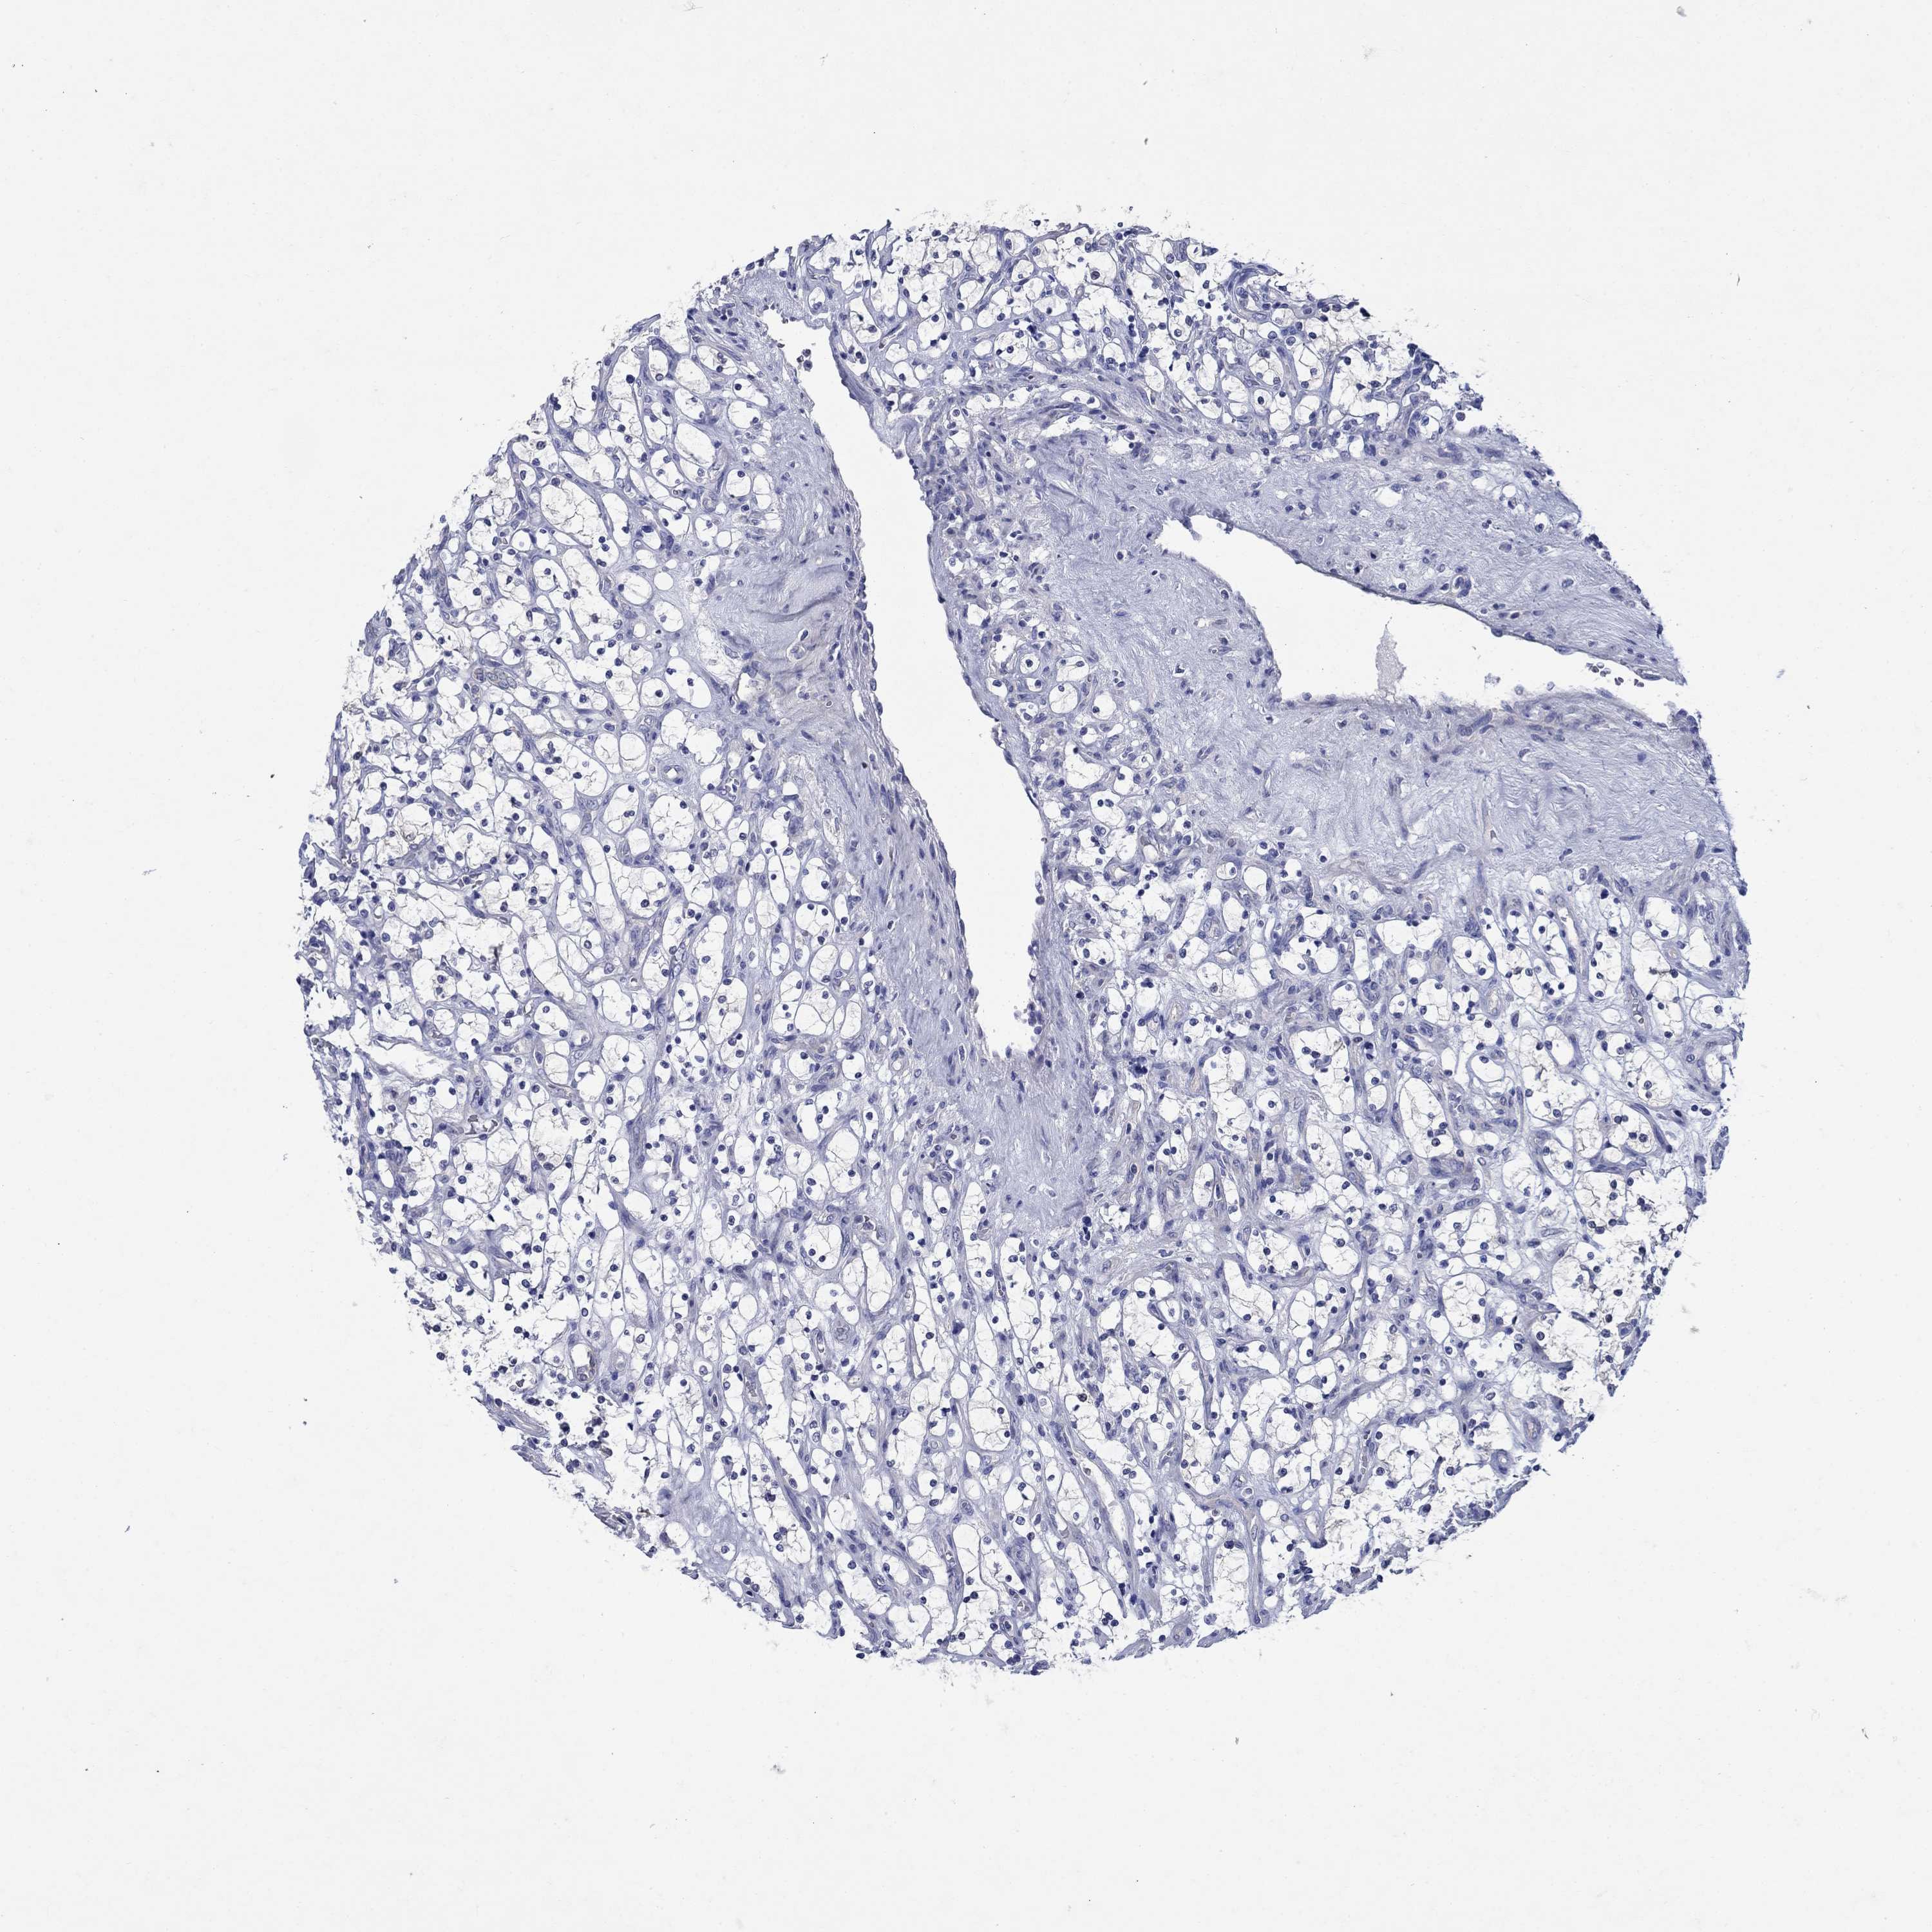

Renal cancer

Kidney renal clear cell carcinoma